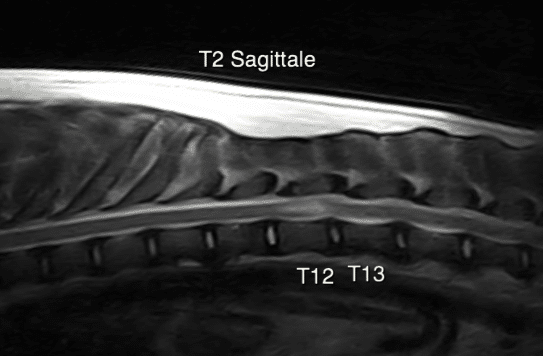

Le myéloscanner

La moelle épinière et les racines nerveuses ne se voient que très peu et avec une mauvaise définition sur un scanner.

Le myéloscanner est une technique d’imagerie qui permet de visualiser les limites de la moelle épinière après injection de produit de contraste dans son espace sous arachnoïdien (sous les méninges).

Il permet de découvrir des déformations de la moelle secondaire à des hernies discale, des anomalies vertébrales, des masses, …